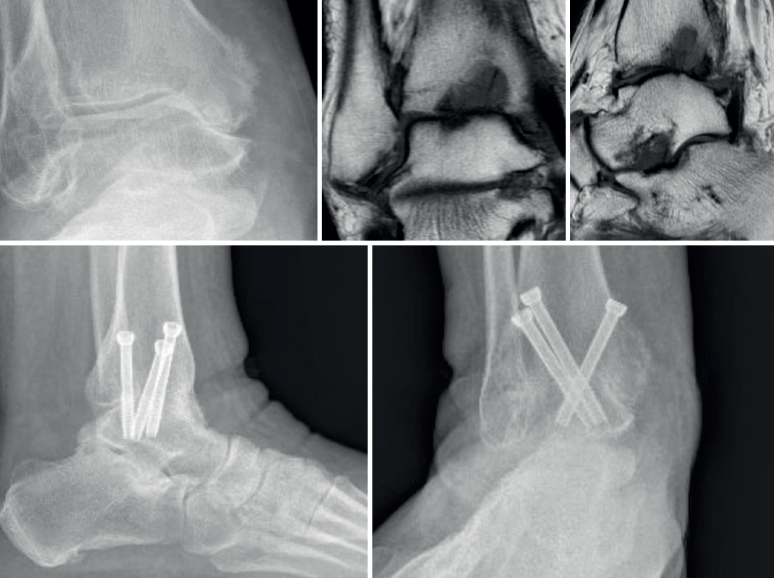

Myerson(20) concluye que la configuración que confiere mayor rigidez a la osteosíntesis es con 2 tornillos desde medial y 1 desde lateral, colocación que compartimos nosotros. Utilizamos tornillos de 6,5 mm de diámetro de rosca parcial, procurando que toda la zona roscada quede alojada en el astrágalo para realizar una adecuada compresión (Figura 2). Es necesaria, por tanto, la radioscopia intraoperatoria.

Figura 2. Imágenes radiográficas en carga y de resonancia magnética preoperatorias. Control al año de evolución tras artrodesis tibiotalar artroscópica.